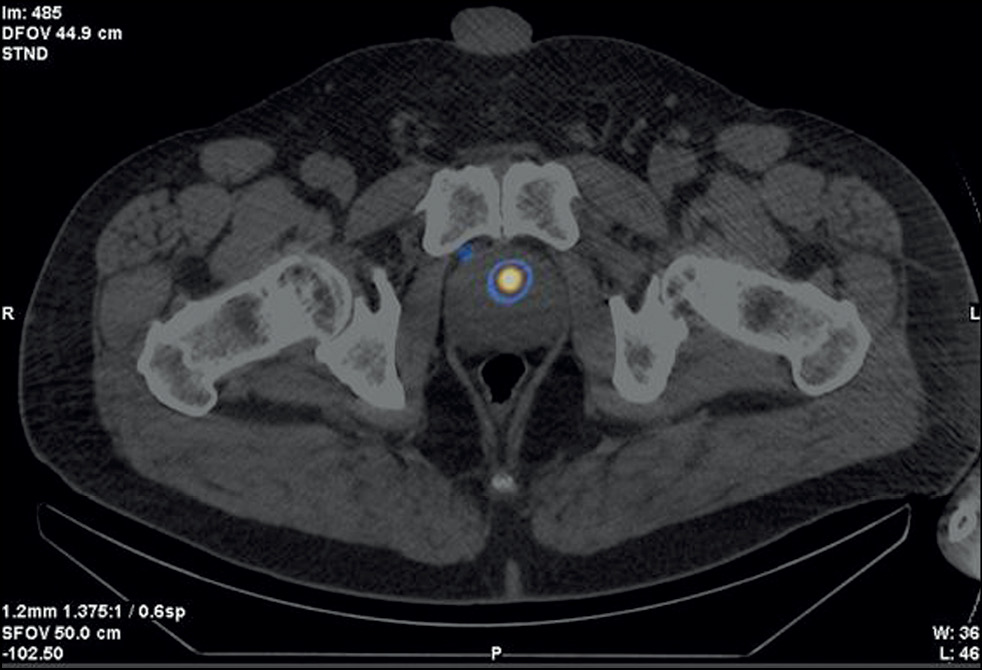

Figure 2 shows SPECT/CT data with 99mTc-HYNIC-PSMA.

Fig. 2. Patient Zh., 8 years old, SPECT/CT with 99mTc-HYNIC-PSMA, axial projection: Site of radiopharmaceutical accumulation in the transition zone of the middle part of the right prostate lobe.